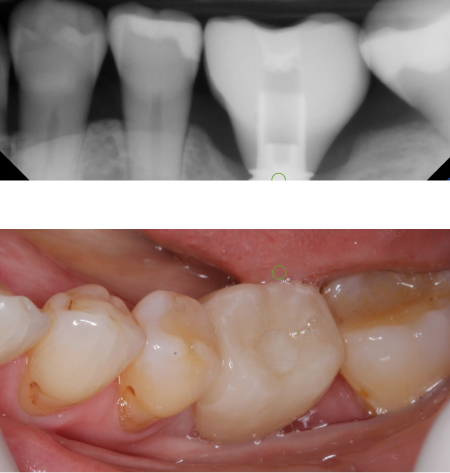

Changes in bite position with comprehensive treatment

When there is insufficient space to restore teeth

Opening the bite position provides a more stable

position also protecting the front teeth

Original bite position

Opened bite with upper restorations